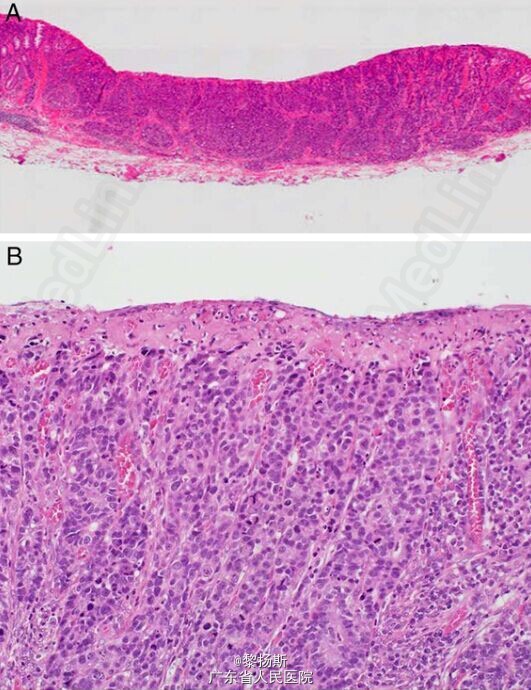

粘膜下注入生理盐水后,病灶隆起,然后行内镜下粘膜切除术。肿物完整切除、无不良情况。 大体检查,肿瘤为 11*5mm 表浅隆起型病变,伴表浅凹陷(图 2)。将标本以 2mm 间隔连续切开。镜下,肿瘤细胞排列成梁状及巢状(图 3A、B),周边可见少许腺癌成分(图 4A)。 免疫组化检查,肿瘤主体神经内分泌标记阳性,如 CgA(图 5A)、Syn(图 5B)、CD56。两种肿瘤成分免疫组化表现类似,二者均为角蛋白 AE1/AE3(图 4B)及 CD10(图 4C)阳性,MUC2(图 4D)、MUC5AC、MUC6 及阿辛蓝阴性。非肿瘤区的粘膜内未见 CgA 阳性细胞巢。肿瘤区核分裂 >20/10HPF,Ki-67 指数 >50%。 术后诊断为神经内分泌癌,粘膜下层微浸润(300μm)、无淋巴结转移。